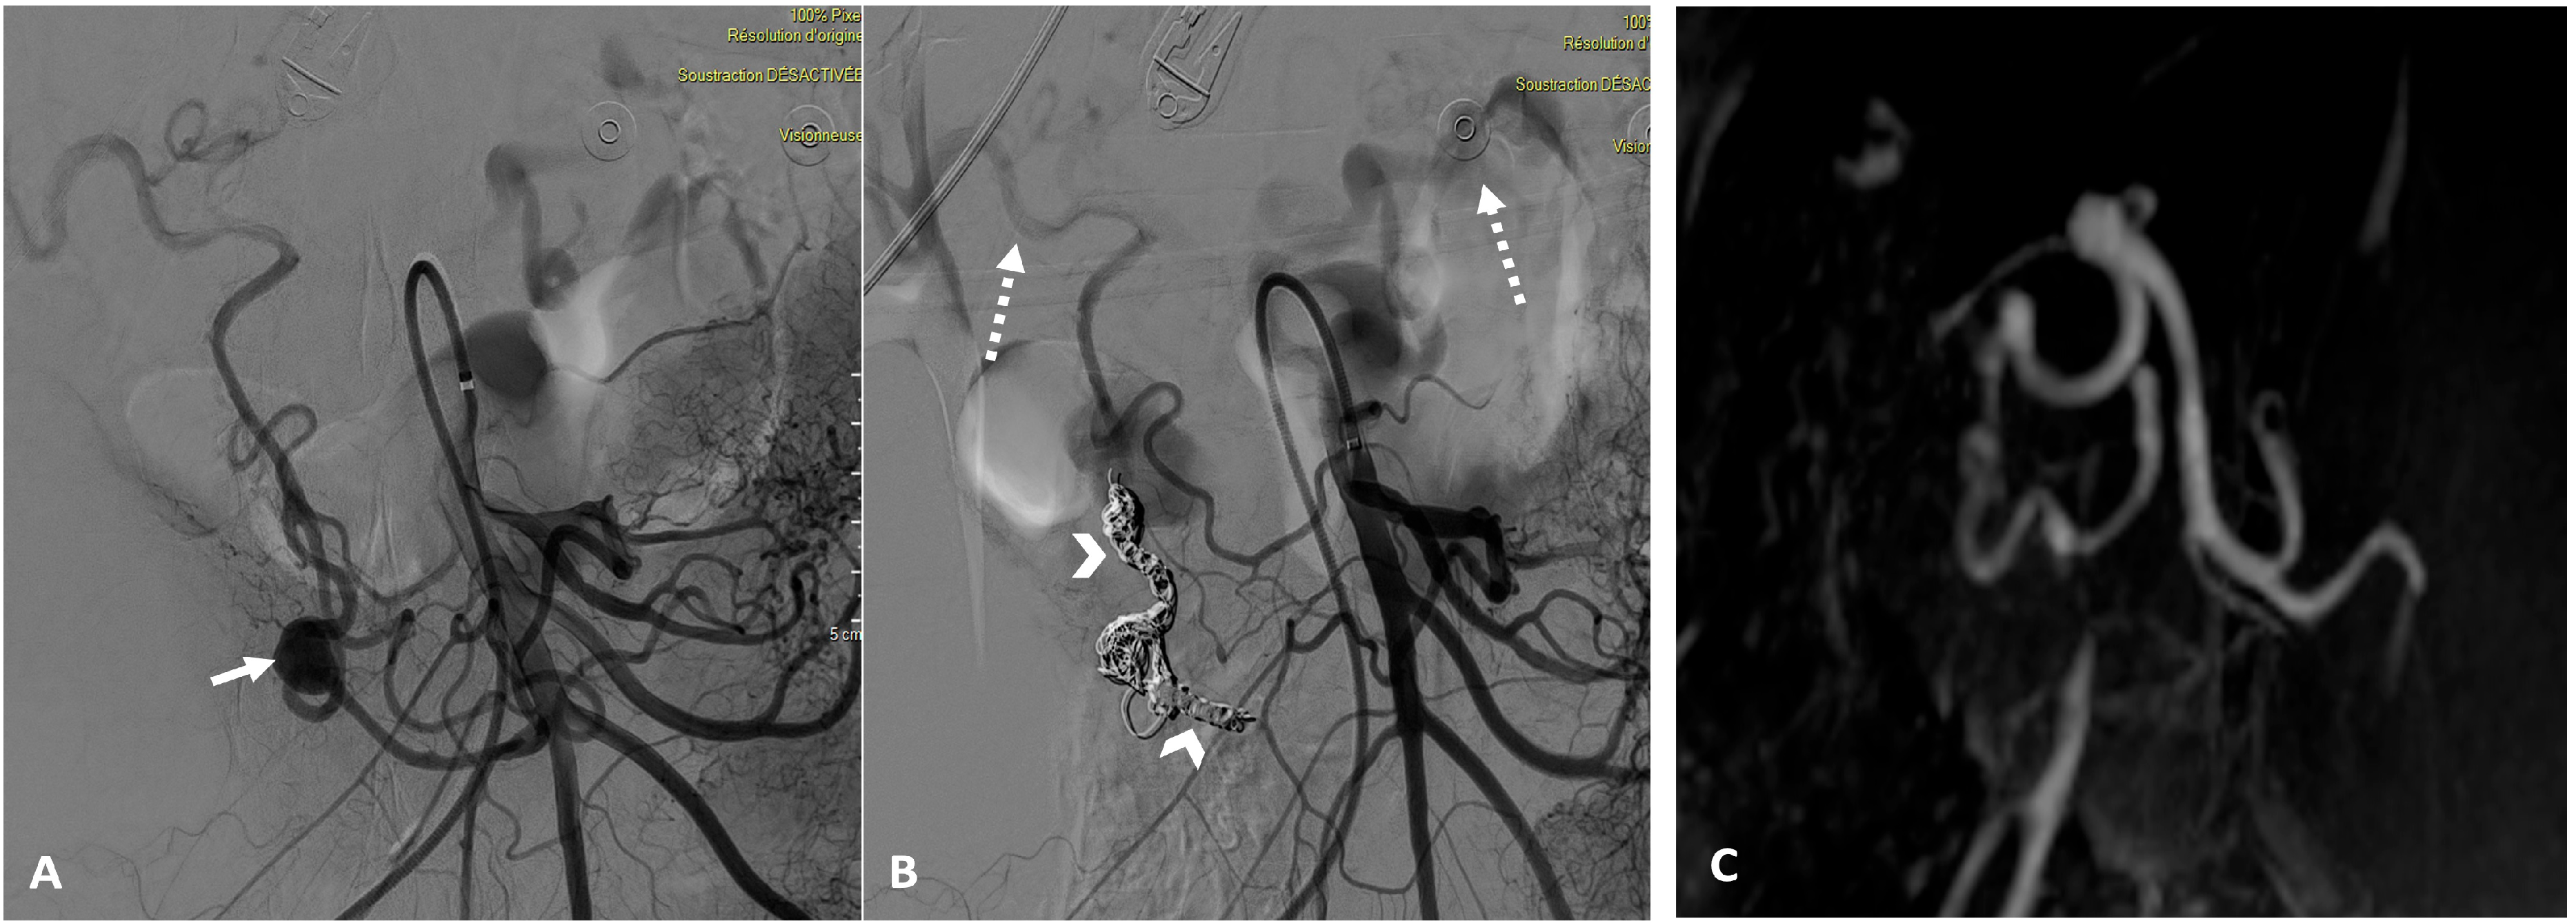

2.3. Embolization Interventions

3.2. Procedure Details

3.3. Technical and Clinical Success

3.4. Embolization Safety